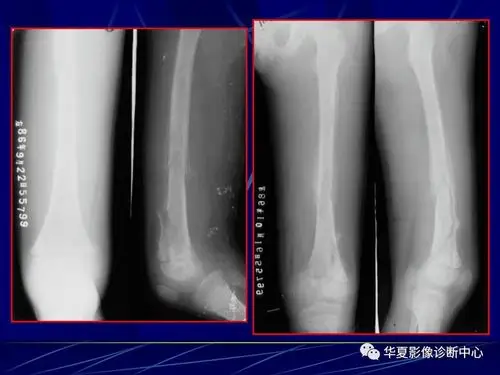

胫骨骨髓炎陈旧骨折如何治疗? [病例帖]

左胫骨近段 急性骨髓炎病例.包秀气 男.9岁

骨化脓性骨髓炎的影像学诊断